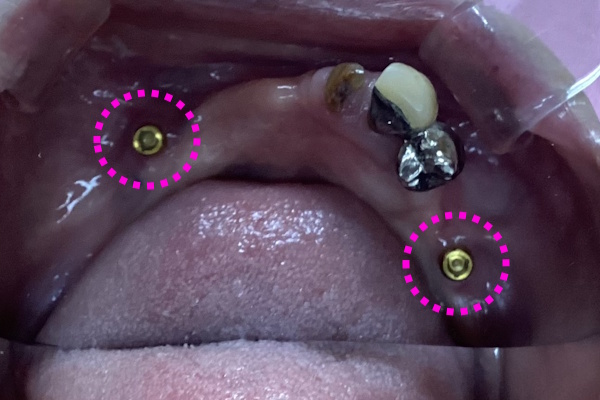

「噛み合わせられない/入れ歯が合わない」ということでご来院いただきました。インプラント治療で快適に噛めるようになりました。下顎はロケーターアタッチメント使用しています。

実際の見た目の写真